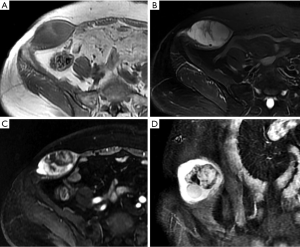

Hematomas present as well-defined, hyperdense rectus masses on unenhanced CT and may show active contrast extravasation on enhanced CT. Their appearance on MRI depends on the stage of the hemorrhage. Deoxyhemoglobin in the acute stage manifests as iso- or hypointense areas on T1WI and T2WI. Methemoglobin in the subacute stage often produces high SI in the form of a peripheral rim, which is a very useful diagnostic factor (Figure 14). In the chronic phase, the dark hemosiderin rim on T1WI and T2WI is a useful discriminating feature (1). CT and MRI help achieve an accurate diagnosis and can be used to evaluate the extent of a hematoma and the presence of active bleeding (3).